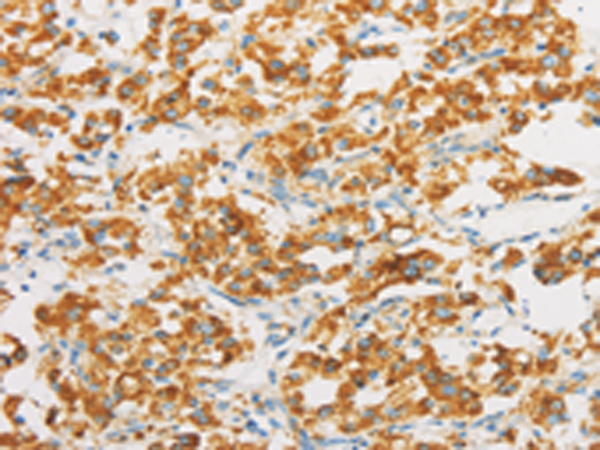

IHC positive control: |

Human thyroid cancer and human cervical cancer |

IHC Recommend dilution: |

25-100 |